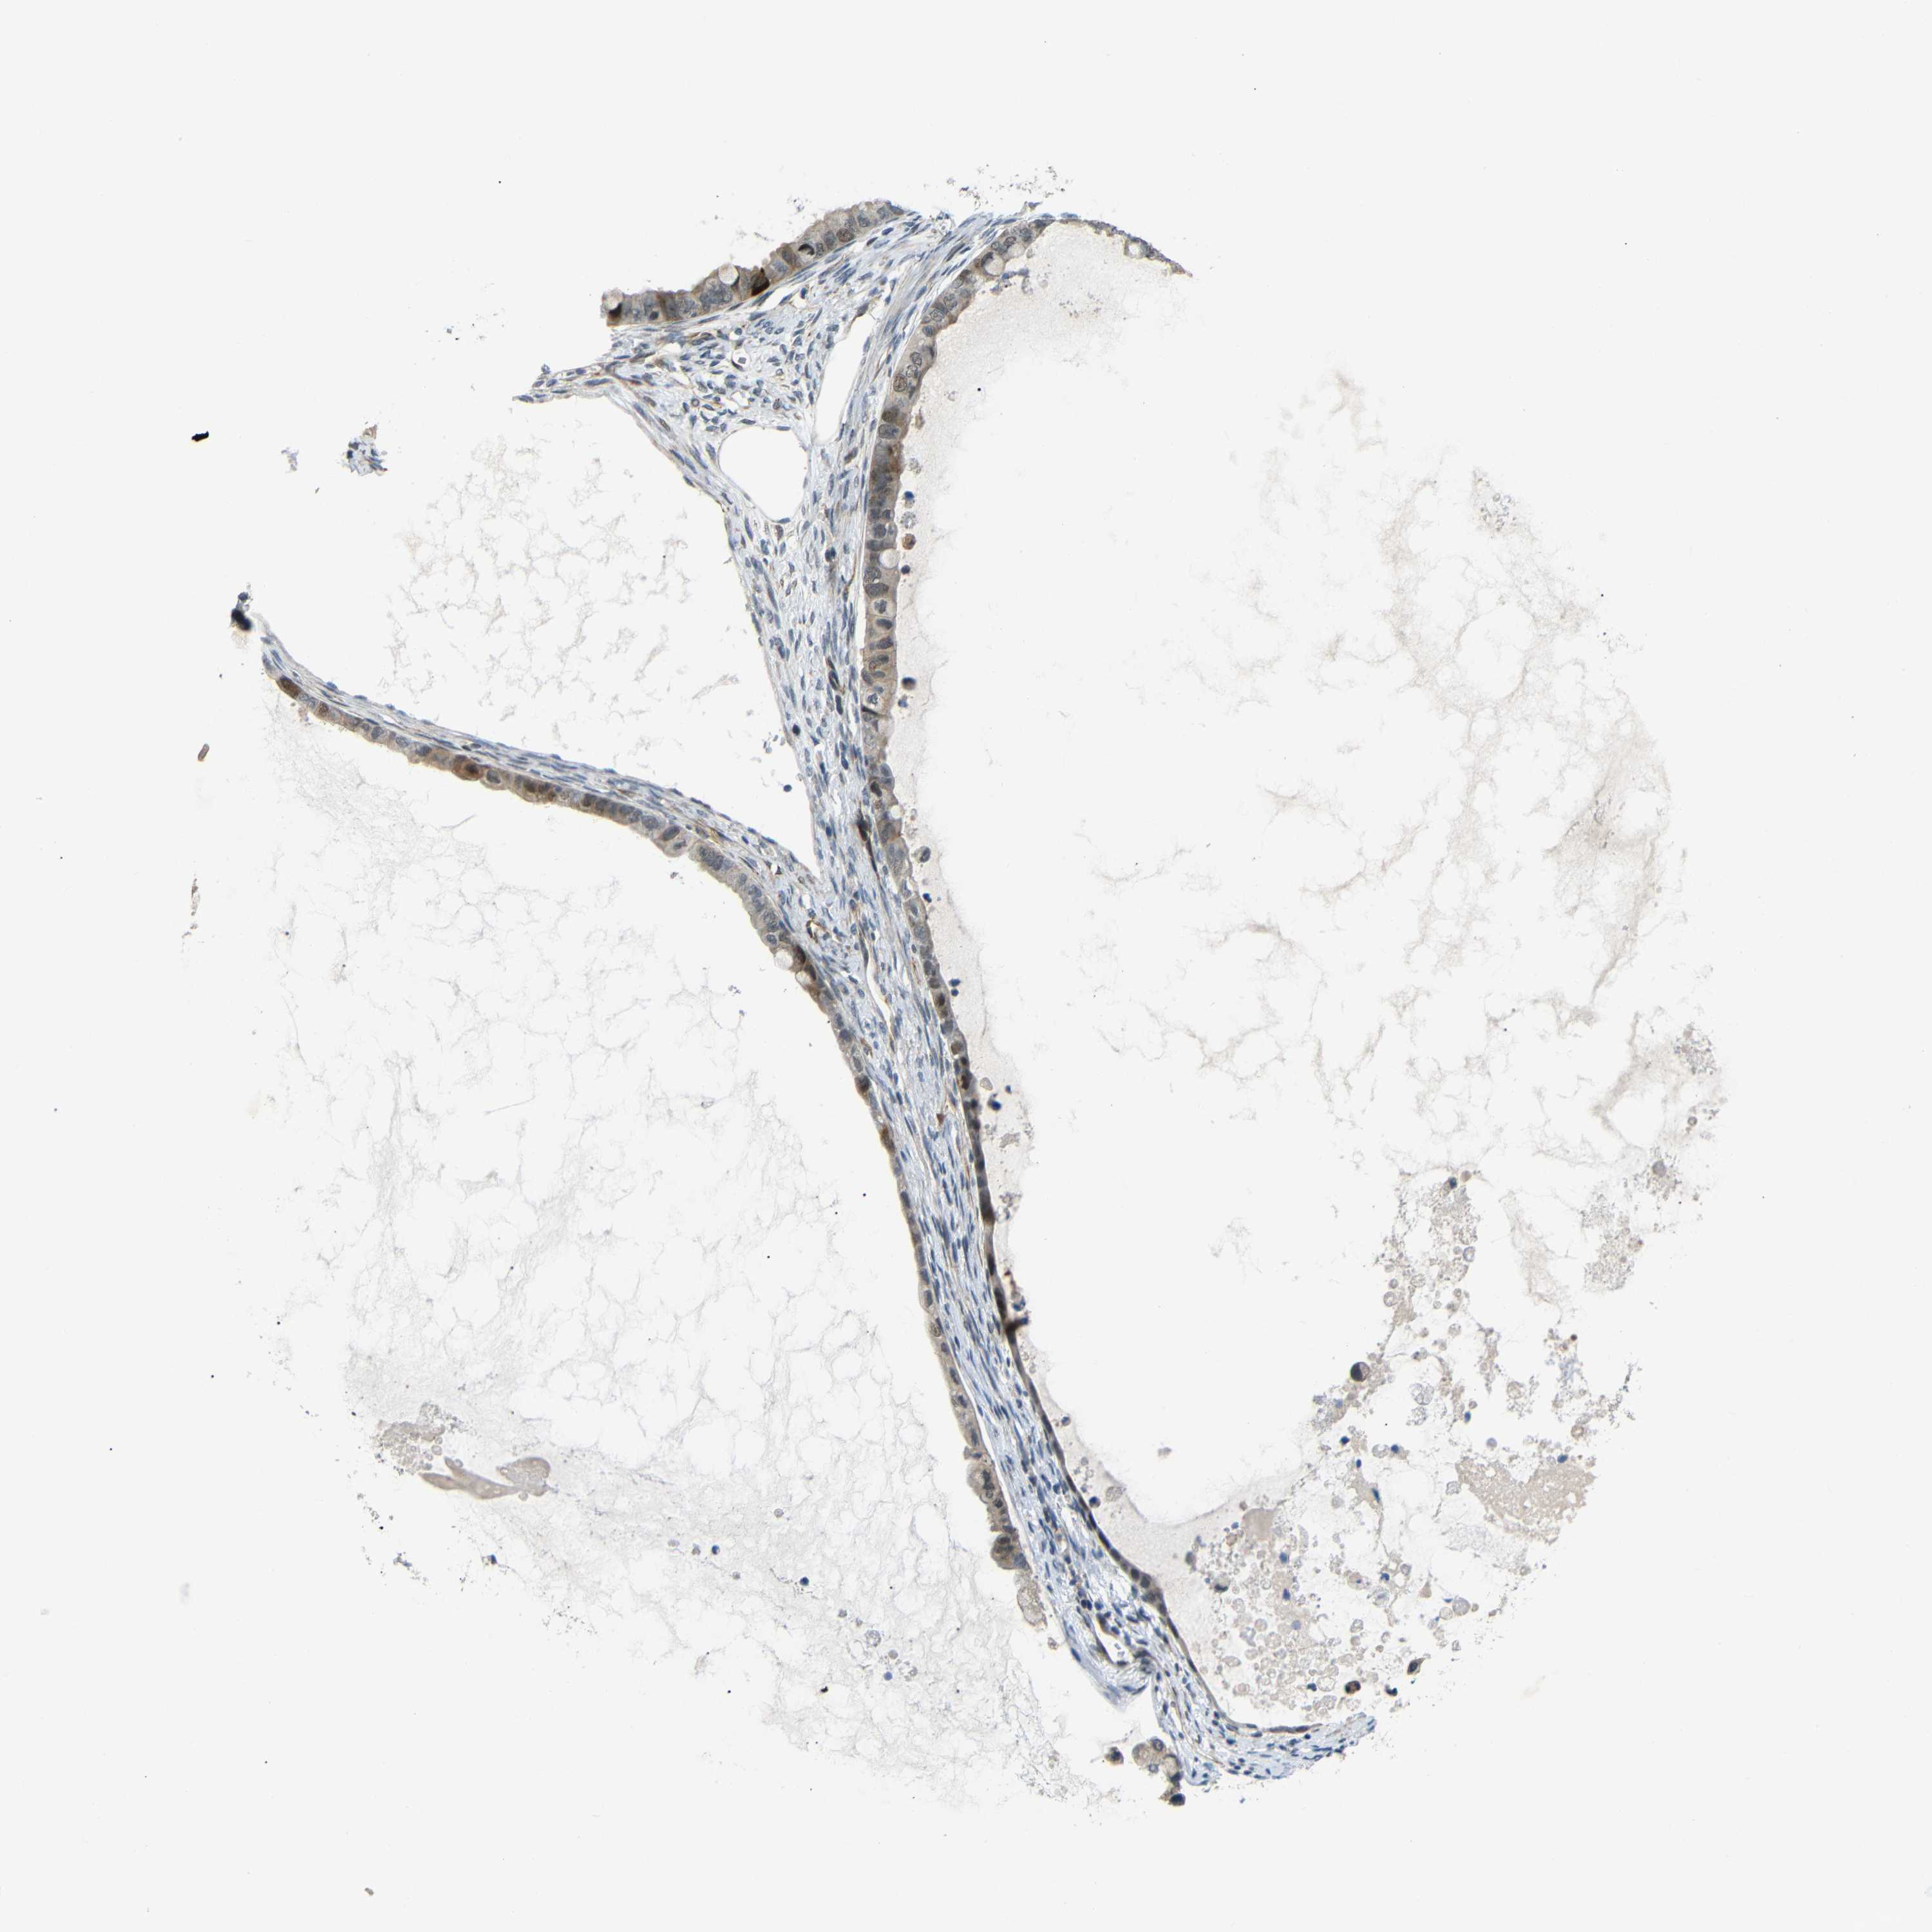

OVARIAN CANCER - Protein expressioni

A mouse-over function shows sample information and annotation data. Click on an image to view it in a full screen mode. Samples can be filtered based on level of antibody staining by selecting one or several of the following categories: high, medium, low and not detected. The assay and annotation is described here.

Note that samples used for immunohistochemistry by the Human Protein Atlas do not correspond to samples in the TCGA dataset.

Antibody stainingi

Antibody staining in the annotated cell types in the current human tissue is reported as not detected, low, medium, or high, based on conventional immunohistochemistry profiling in selected tissues. This score is based on the combination of the staining intensity and fraction of stained cells.

Each image is clickable and will lead to virtual microscopy that enables deeper exploration of all samples and also displays staining intensity scores, fraction scores and subcellular localization as well as patient and tissue information for each sample.

Antibody HPA013328

Cystadenocarcinoma, serous, NOS

Carcinoma, endometroid

Cystadenocarcinoma, mucinous, NOS

Carcinoma, NOS